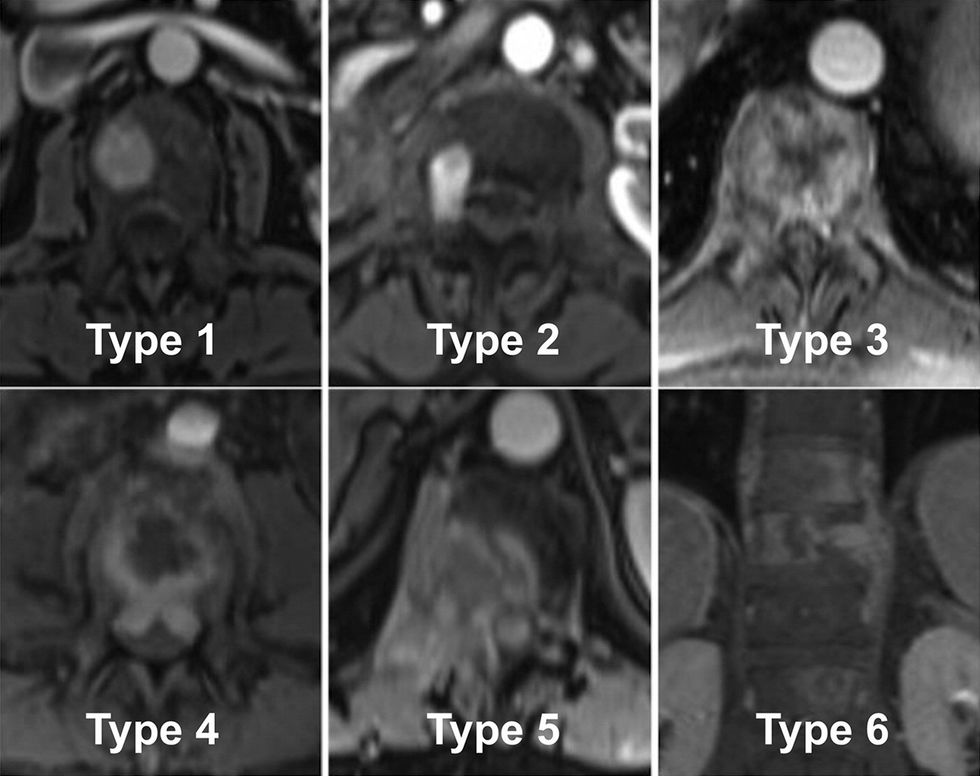

Sipas një analize të publikuar nga American Journal of Gastroenterology, 3% deri në 20% e pacientëve me karcinomë hepatike zhvillojnë metastaza kockore, dhe rreth 50–75 % e tyre ndodhin në shtyllën kurrizore.